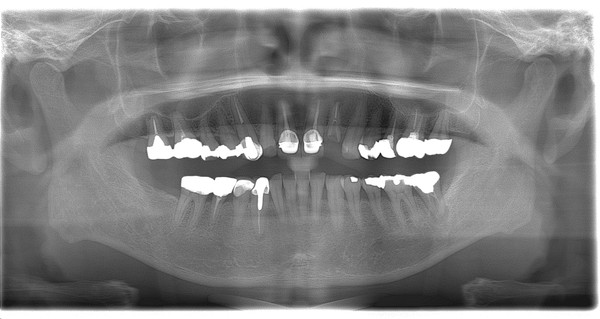

治療内容としては、マイクロエンド、ファイバーコア、セラミック補綴、インプラント、歯周外科などです。

初診時

現在